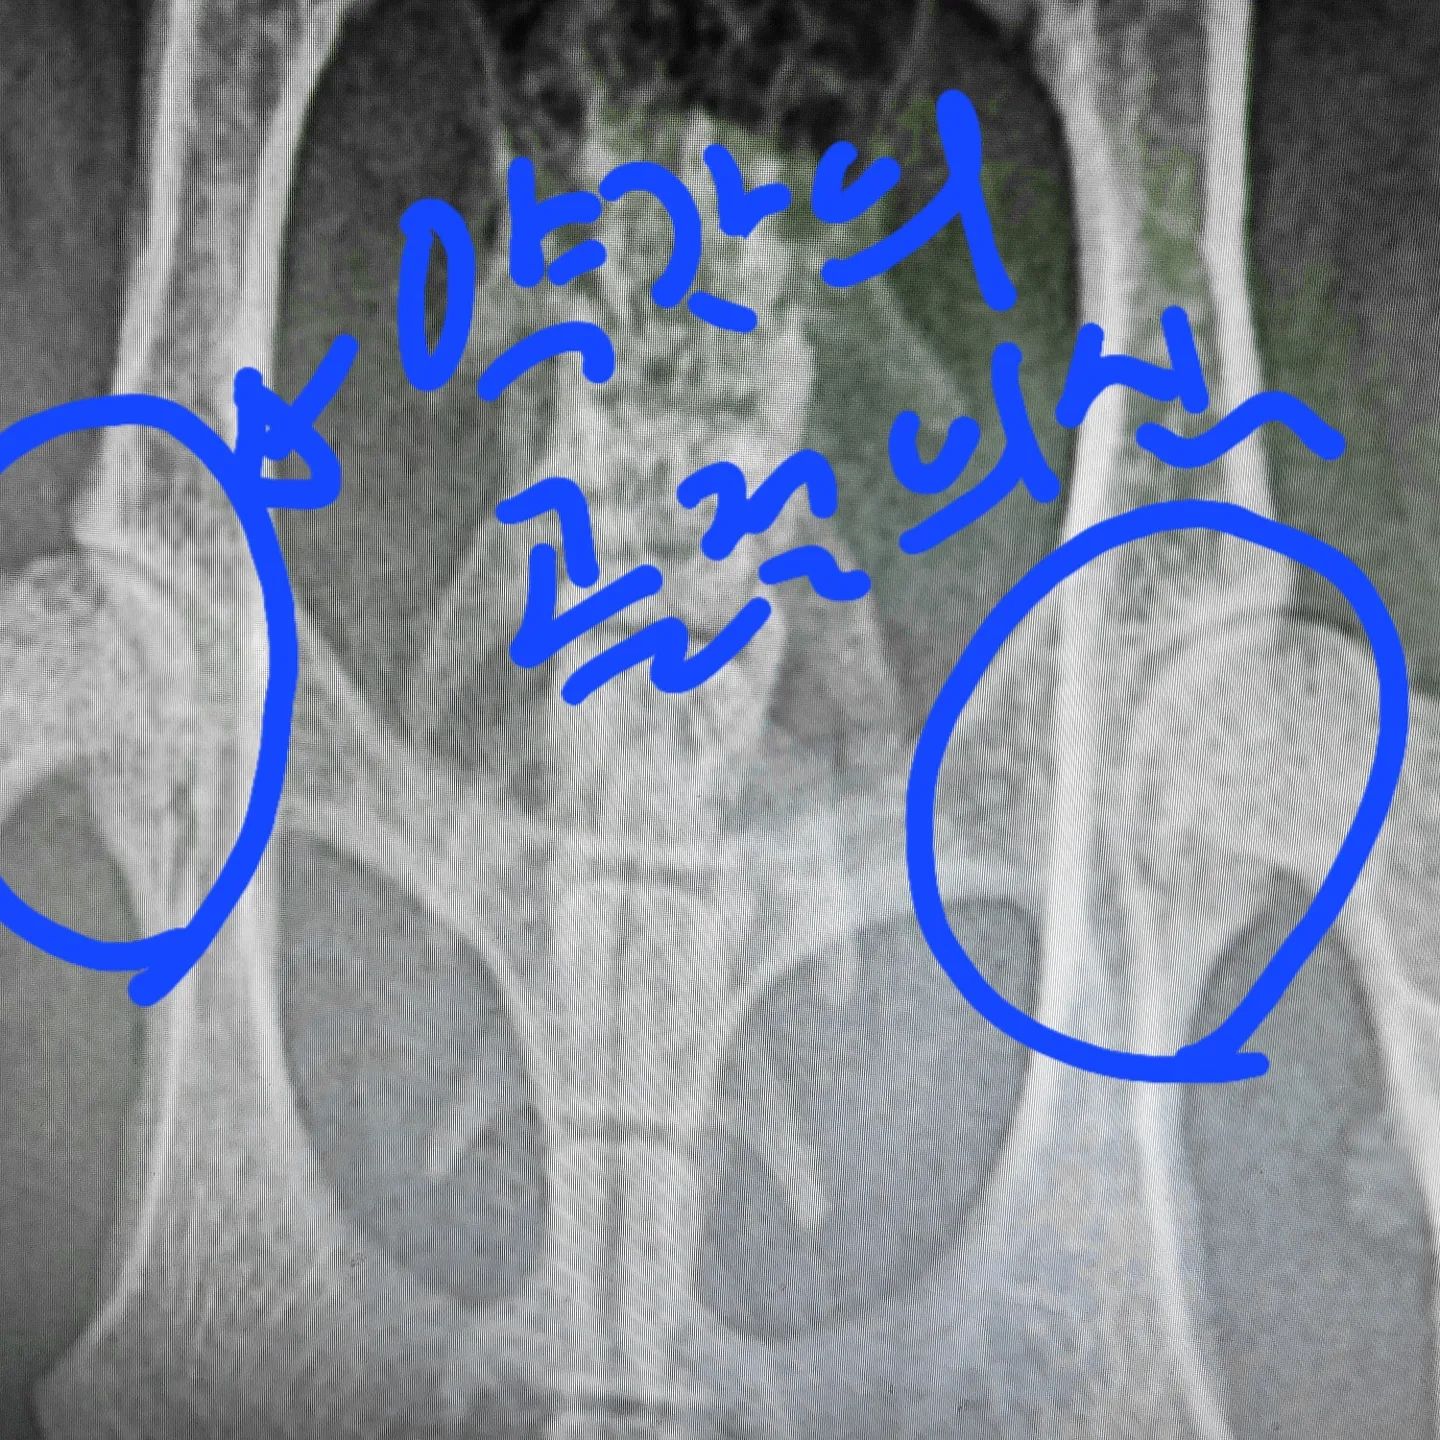

엑스레이를 무려 4번을 찍고 나서야 또리 뒷 다리 골두가 깨졌음을 확인이 가능했습니다. ㅜ.ㅜ

다행히라 해야 할지 모르겠지만 다리 뼈가 깨진것을 발견을 해서야 여기 문제라는 것을 알게되었습니다.

이 엑스레이가 3번째였습니다.. 이때는 진통제를 먹어보고 똑같이 아프다고 보이면

꼭 다시 데려오라고 하셨습니다.. (동네동물병원이 아닌 2차 병원임)

그래서 또리가 다시 아프다고 울어서.. 확인하니

확실히 깨져 있더라구요.. 처음에는 너무 속상한 나머지 이런 생각도 했습니다.

한쪽이 깨지거나 하는 경우는 있는데 양쪽다 깨지기는 어렵다고..

위에 있는 사진처럼 대퇴골두를 절단하는 방법!!

여기를 절단하면나중에 근육들이 생겨나면서 뼈와뼈를 잡아주어 근육이 골두의 역할을

하기 때문에 괜찮다고 합니다.